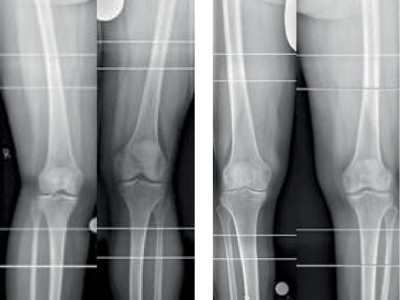

Haben Frauen wirklich häufiger X- und Männer O-Beine?

Laut der bislang überschaubaren Datenlage scheinen Frauen eher zur X‑Beinachse zu neigen, während Männer eher O‑Beine haben. Stimmt das? Um die orthopädisch weitreichende Frage nach genderspezifischen Normwerten zu klären, hat ein Team am Klinikum Bamberg 713 gesunde Beine durchleutet.

Untersuchung des Beins eines Patienten/© Visionär / Fotolia, Sonographiequerschnitt über der Hälfte des M. quadriceps (Normalbefund)/© Gehlen M et al. / all rights reserved Springer Medizin Verlag GmbH, Eine Frau hält sich den Fuß am Knöchel/© dragana991 / Getty Images / iStock (Symbolbild mit Fotomodell), ZFA TALKS - Nackenschmerzen/© (M) contrastwerkstatt / Stock.adobe.com (Symbolbild mit Fotomodell), Fortgeschrittene Gonarthrose bei 83-Jähriger/© J. Stöve, Arzt untersucht Senior am Rücken/© miodrag ignjatovic / Getty Images / iStock (Symbolbild mit Fotomodellen), Frau mit Hut im Wald/© (M) encierro / stock.adobe.com (Symbolbild mit Fotomodell), Frau bei Knochenmineraldichte-Messung/© gelmold / stock.adobe.com (Symbolbild mit Fotomodell), Arzt untersucht Patienten mit Rückenschmerzen /© ChesiireCat / Getty Images / iStock (Symbolbild mit Fotomodellen), Frau geht Spazieren/© HODEI / stock.adobe.com (Symbolbild mit Fotomodell), Messung des Kopf-Wand-Abstands/© A. Schuh, Schmerzhafte Schwellung des linken Ellenbogens/© C. Raschka, Hallux rigidus Röntgenbefund/© A. Schuh, Coxarthrose rechts nach Kellgren-Lawrence-Grad III/© Dres. Lieser und Kollegen, Radiologische Praxis Trier, Sonografie am Fußgelenk/© A. Schuh, Gelenkultraschall am Knie/© A. Schuh, MRT bei medialseitiger Gonarthrose mit Knorpelschaden/© Klinikum rechts der Isar, Ultraschall am Ellenbogen/© A. Schuh, Position des Schallkopfs ventral an der Schulter/© So wie es am Bild steht, Röntgenaufnahmen von Valgus- und Varusachsen/© Schubert I et al. / all rights reserved Springer Medizin Verlag GmbH, Achillessehnenruptur/© Z. Binder, Ärztin behandelt Fußballspielerin mit Kopfverletzung/© rocketclips / stock.adobe.com (Symbolbild mit Fotomodell), Patientin mit Gonarthrose/© (M) FluxFactory / Getty Images / iStock (Symbolbild mit Fotomodellen), Search Icon, Die Leitlinien für Ärztinnen und Ärzte, Facharzttraining Allgemeinmedizin, Hand hält Laborröhrchen/© Kunstzeug / stock.adobe.com (Symbolbild mit Fotomodell), Läufer umfasst sein Sprunggelenk/© PeopleImages / Getty Images / iStock (Symbolbild mit Fotomodell), Herpes Zoster am Rücken/© Mumemories / Getty Images / iStock (Symbolbild mit Fotomodell), EKG befunden mit System - EKG Essential/© Springer Medizin Verlag GmbH